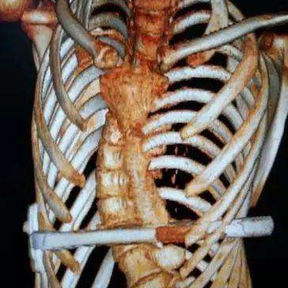

The patient was diagnosed with severe complex chest wall deformities accompanied by scoliosis. The heart was severely compressed and shifted to the left thoracic cavity.

We developed a personalized surgical plan for the patient. The operation first involved making incisions along the surgical scars on both sides of the chest wall to remove the bar inserted during the Nuss procedure. Then, a larger incision was made at the central scar on the anterior chest wall to fully expose the bone structure located at concave and convex areas of the chest wall. It was found that there were severe adhesions between the chest wall structure and the pericardium, with the heart being compressed into the left chest cavity.

​First, the adhesions were thoroughly released, and a portion of the protruding ribs and costal cartilage at the top of the protrusion was cut off. By lifting and pressing down, the chest wall was adjusted to its normal height. Second, three MatrixRIBs was used to replace the removed rib sections, and their curvature was carefully adjusted to closely resemble the normal curvature of the chest wall, thereby completing the reconstruction of the thoracic cage. Third, a bar was placed and flipped within the chest wall to elevate the most depressed part of the central chest wall. Lastly, two bars were placed on and secured to the bone surface of the lower half of the chest wall. The surgery achieved a satisfactory result, eliminating the deformities and restoring the chest wall to its normal shape.